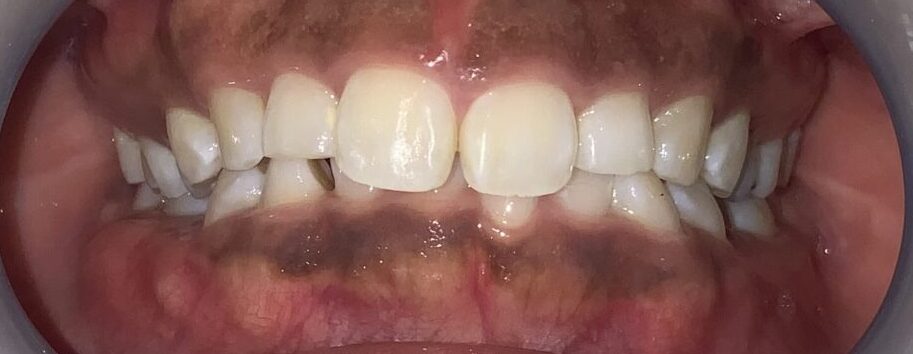

一番気になる、前歯の歯と歯ぐきの位置状態の検査します。

こんなに歯ぐきがかぶさっています。

反対側の歯も調べてみます。前歯の形はとても大切ですから、慎重に検査を進めます。

この歯も同じように、たくさんの歯ぐきが、かぶさっています。